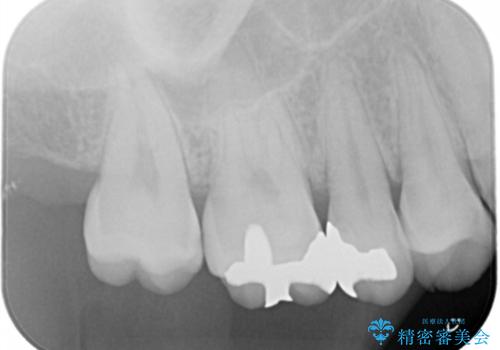

- 銀の詰め物を白くしたいとの事で来院。

拡大鏡下で詰め物を外しう蝕がないことを確認して、e-maxインレーにて治療しました。

- e-maxインレー 7.7万円 費用は治療当時の料金となります

セラミックの詰め物は歯質とピッタリ適合して虫歯の再発率が低いです。